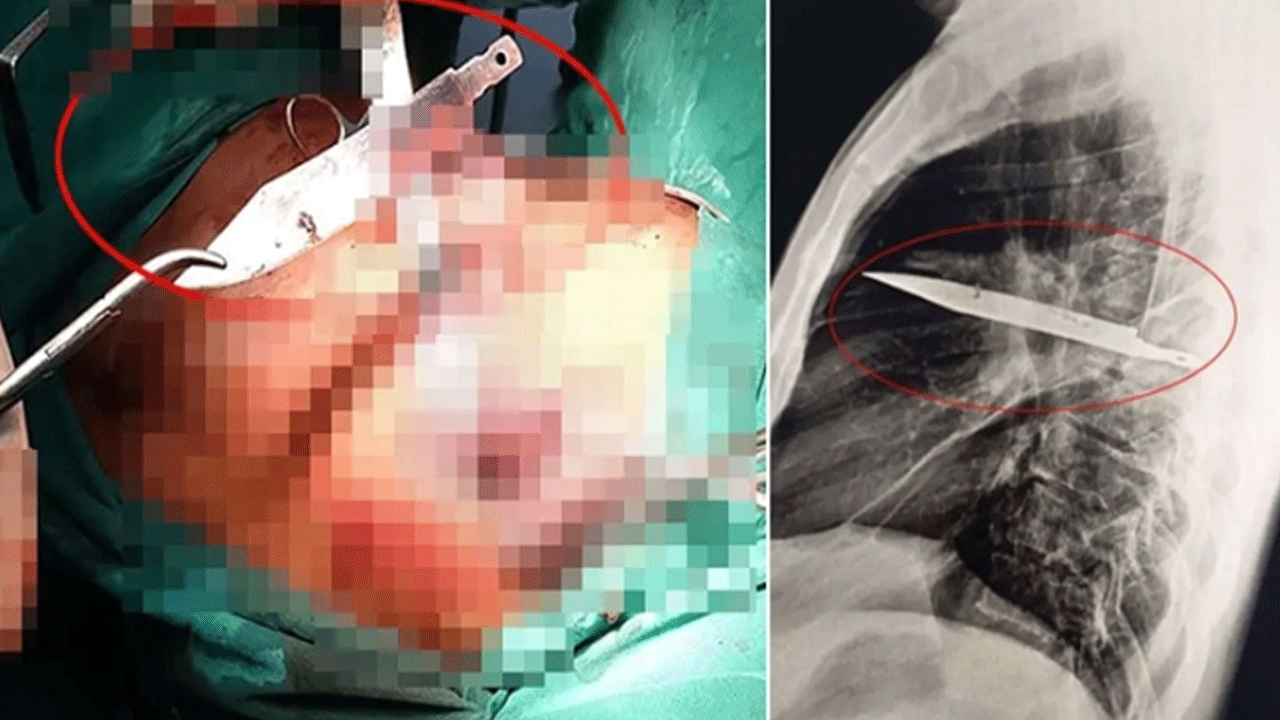

Tanzanya’da bir kişi, göğüs ağrısı ve iltihap şikâyetiyle gittiği hastanede şoke edici gerçekle yüzleşti. Doktorlar, göğsünde tam sekiz yıldır saplı duran bıçağı ameliyatla çıkardı.

Ancak yapılan röntgen sonucu herkesi şaşkına çevirdi. Adamın göğsünde tam 8 yıldır saplı duran bir bıçak vardı.

Bıçağın sağ kürek kemiğinden girerek hayati organlara zarar vermeden göğüste kaldığı belirlendi.

Yapılan ameliyatla bıçak çıkarıldı ve ölü dokular temizlendi.